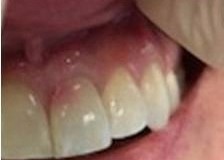

This young patient was self-conscious about the appearance of her short teeth and gummy smile. Through crown lengthening and tooth whitening procedures, we were able to create a beautiful, more mature smile.